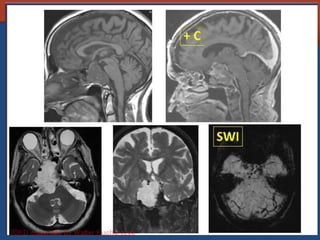

Pituitary Macroadenoma

• Usually soft

• Elevate diaphargma selle

• Often contrasted at diaphargmatic hiatus as

tumor growth into the suprasellar cistern

• Snowman shape

• *commonest large tumor of the skull base

Pituitary apoplexy

• Predisposing by: pre-existing macroadenoma,

pregnancy (Shehan syndrome)

• Associated with SDH, SAH, visual loss, acute

pituitary insufficiency.